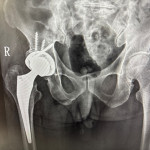

• DAA微創髖關節手術 助病人快速恢復行動力 (10:47)

DAA微創髖關節手術 助病人快速恢復行動力

76歲男性多年前因髖臼骨折接受手術,術後留下垂足(foot drop)與步態異常,長期行動不便,導致外傷性退化性髖關節炎,連如廁與行走都成為挑戰。經新竹臺大分院骨科團隊詳細評估並與病人充分溝...